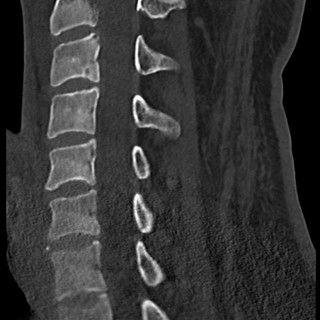

En jente i tenårene ble innlagt ved barneavdelingen grunnet kjevesperre, hevelse på halsen og mistanke om peritonsillær abscess. Utredningen skulle avdekke et mer komplekst symptombilde enn forventet ut fra innleggelsesårsak. En ung jente, fra tidligere vesentlig frisk foruten pollenallergi, ble innlagt etter to ukers sykehistorie med halssmerter. Hun var tidlig i forløpet vurdert hos fastlegen, der hurtigtest for mononukleose (Monospot) var negativ. Tilstanden ble tolket som tonsillitt, og pasienten fikk forskrevet en kur med peroral fenoksymetylpenicillin. Grunnet svelgsmerter ble ikke...